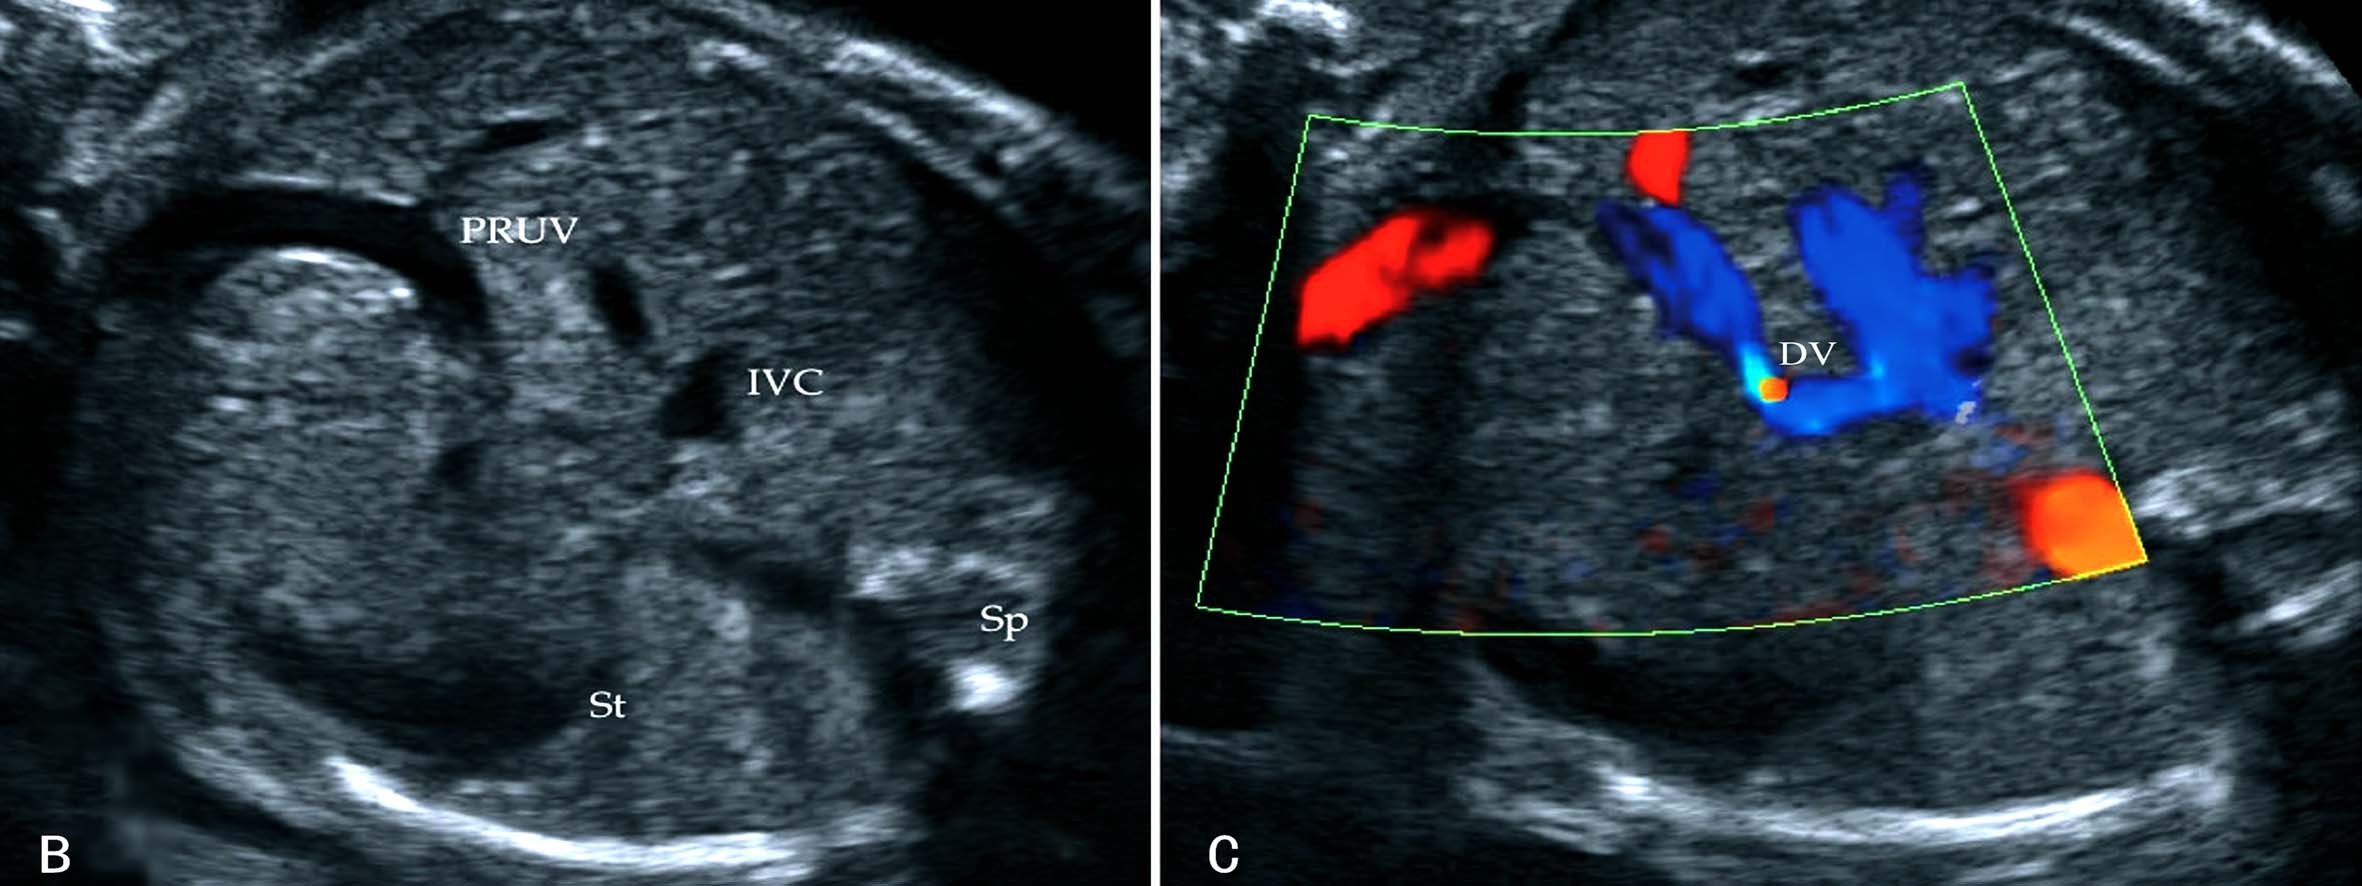

胎儿腹部横切面显示胃泡和脐静脉以后观察胆囊的位置可以确定脐静脉走行。正常脐静脉穿过脐轮后走行于胆囊的左侧,在胆囊与胃腔之间可以显示脐静脉的回声(图8A);如果在胆囊右侧显示脐静脉回声即可明确右脐静脉的诊断((图8B));肝内型持续性右脐静脉进入肝脏后PRUV需要转向左侧与静脉导管连接(图9)。连续追踪扫查如果显示脐静脉周围或一侧无肝脏实质,则提示为肝外型持续性右脐静脉。一般认为,后者常合并其他部位的发育异常,并可以合并染色体异常。

图8 正常脐静脉与持续性右脐静脉声像图比较

图11-54 持续性右脐静脉声像图